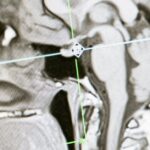

La décompression spinale est une technique non invasive utilisée pour alléger la pression sur les disques intervertébraux et les nerfs. En créant un espace entre les vertèbres, cette méthode aide à réduire la douleur et à favoriser la guérison. Les patients souffrant de problèmes tels que les hernies discales ou les douleurs chroniques du dos bénéficient souvent de cette approche.

La décompression spinale repose sur des techniques non invasives qui visent à réduire la pression sur les disques intervertébraux et les nerfs de la colonne vertébrale. Elle est particulièrement efficace pour traiter des conditions comme les hernies discales, la sciatique et d’autres douleurs chroniques. En améliorant la circulation sanguine et en soulageant la tension, cette méthode favorise une récupération plus rapide et durable.

La décompression spinale agit en exerçant une traction douce sur la colonne vertébrale, créant ainsi un espace entre les vertèbres. Cette méthode relâche la pression sur les disques intervertébraux, permettant une meilleure circulation sanguine et une réduction de l’inflammation. Pour les athlètes, cela signifie un retour rapide à leurs activités sportives, sans la crainte de douleurs persistantes.

La décompression spinale fonctionne en réduisant la pression exercée sur les disques intervertébraux et les nerfs spinaux. Cela facilite la circulation sanguine et aide à éliminer l’inflammation, ce qui est essentiel pour la guérison. Cet aspect est particulièrement utile pour les athlètes qui cherchent à reprendre leurs activités sportives après une blessure. En améliorant la santé des disques, cette méthode augmente non seulement le confort, mais renforce également la confiance des sportifs dans leurs capacités physiques.

La décompression neurovertébrale est une méthode thérapeutique non invasive qui pourrait bien être votre solution. Spécialement conçue pour soulager les douleurs associées aux pathologies discales sévères telles que la hernie discale et le pincement discal, cette approche utilise une traction douce et contrôlée pour étirer votre colonne vertébrale. Grâce à cette technique, la pression sur les disques intervertébraux et les nerfs environnants est réduite, permettant ainsi une guérison efficace des tissus endommagés. Si vous avez déjà essayé d’autres traitements comme la physiothérapie ou les médicaments sans succès, il est temps de découvrir une solution qui pourrait véritablement changer votre quotidien.